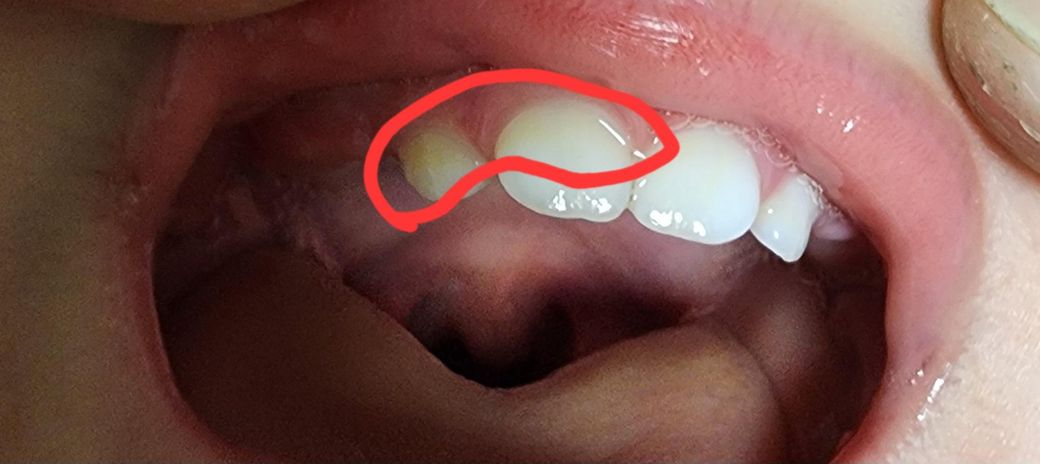

아기 치아 충치일까요?..한번만 봐주세요ㅠㅠ

15개월아기 아침,저녁 불소치약으로 칫솔질해주고 마무리로 실리콘으로 입안에 닦아줘요!

오늘 우연히 치아를 보니 저 부분이 약간 짙은 노란색처럼 됬어요ㅠㅠ 충치인지 착색된건지..궁금해요ㅠㅠ

• 1번 째 사진